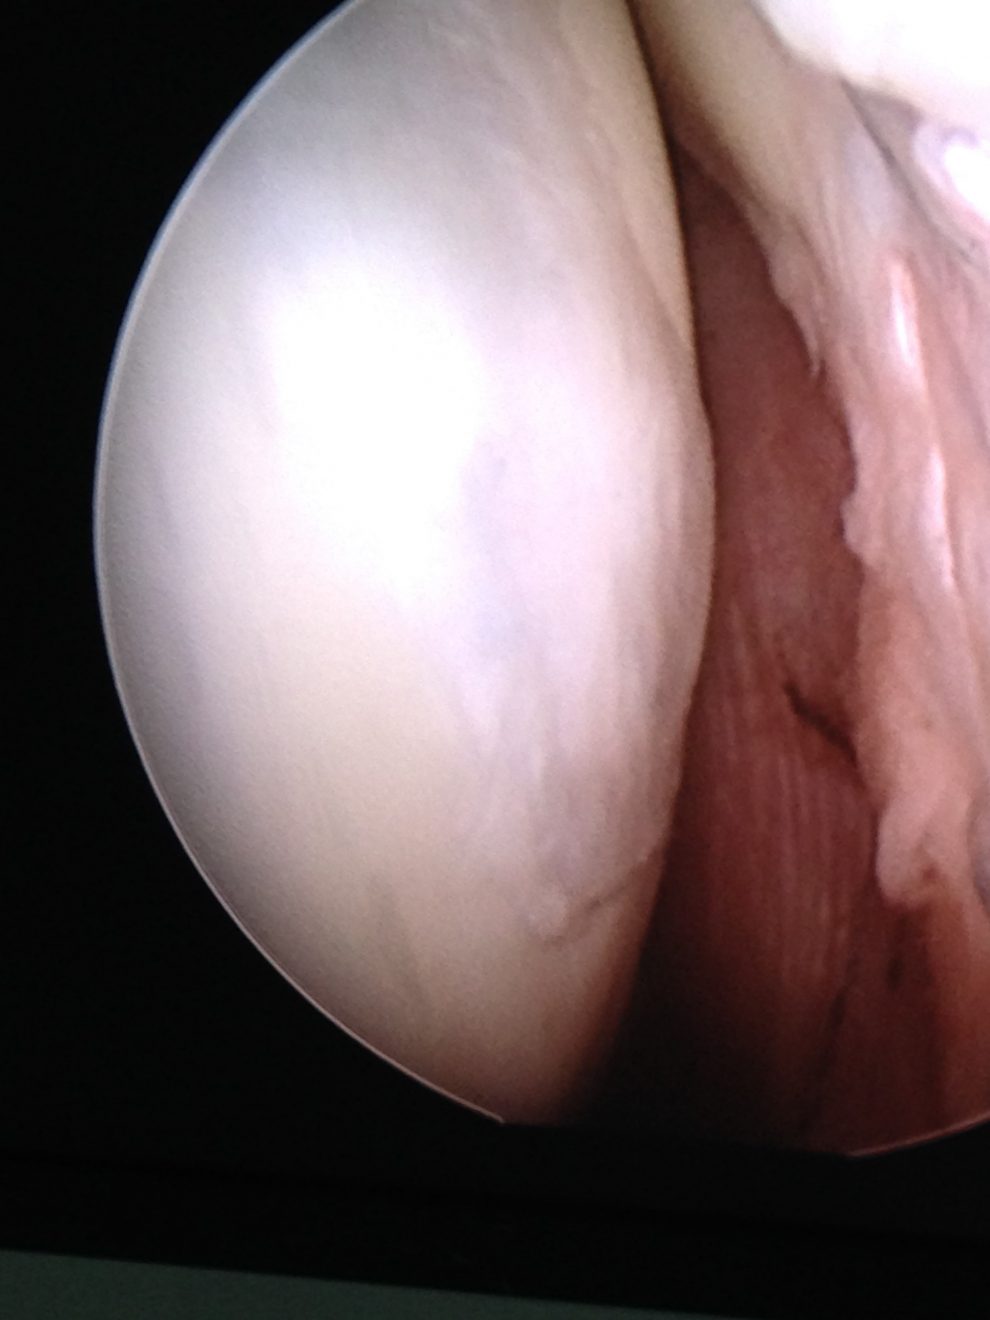

- wykonać zabieg artroskopii stawu. Możemy poddać leczeniu praktycznie wszystkie elementy stawu kolanowego, naprawiając łąkotkę, stymulować chrząstkę do naprawy, rekonstruować więzadła. Choć chrząstka szklista w stawie nie regeneruje się do nowej chrząstki, poprzez wykonanie zabiegów naprawczych, które polegają na oczyszczeniu uszkodzonej powierzchni chrzęstnej, a następnie wykonaniu mikrozłamań, nawierceń lub implantacji specjalnych węglowych pinów, aktywizujemy komórki szpiku (komórki mezenchymalne), które mają bardzo duży potencjał biologiczny. Pokrywają one uszkodzoną powierzchnię chrzęstną i wypełniają ubytek tkanką chrzęstną włóknistą, która nie jest chrząstką szklistą, ale bardzo ją przypomina. Zabieg ten uwalnia pacjenta od bólu i poprawia jakość jego życia.

Obrazy z artroskopii stawu